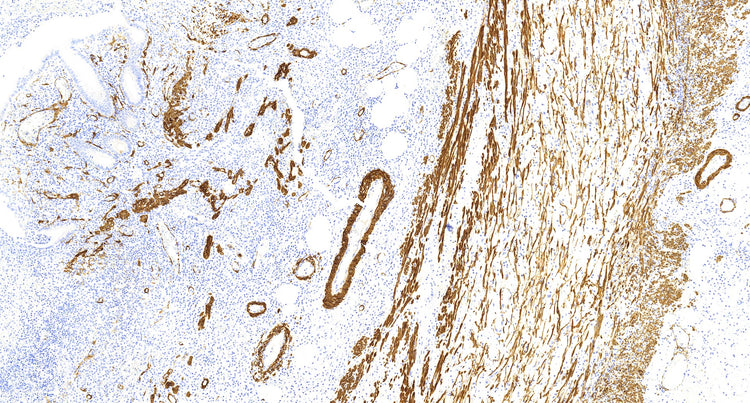

El marcador de actina del músculo liso (SMA) se ha utilizado ampliamente en diversos contextos. Los dos anticuerpos comúnmente utilizados para la detección de AME son el anti-SMA y la actina específica del músculo (clon HHF-35). La AME se conoce como un marcador sensible para la diferenciación mioepitelial. Sin embargo, carece de especificidad ya que cualquier célula con una expresión significativa de actina mostrará una tinción positiva para AME. En el tejido mamario, los miofibroblastos y los vasos sanguíneos suelen tener una tinción positiva para AME. Esto puede plantear desafíos en los casos en los que hay miofibroblastos o vasos sanguíneos muy cerca de la lesión epitelial que se examina, como en la adenosis esclerosante, las cicatrices radiales, las lesiones papilares o el carcinoma ductal in situ (CDIS).

A pesar de su falta de especificidad, la AME sigue siendo un marcador útil debido a su alta sensibilidad. Ayuda a resolver el diagnóstico diferencial en un número importante de casos. Al considerar el patrón de tinción y el contexto, los patólogos pueden interpretar los resultados y diferenciar entre diferentes lesiones.